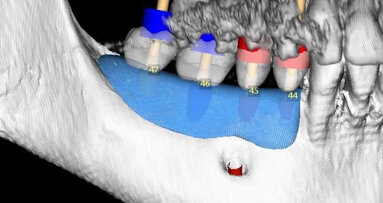

Nicméně, štěp je nutno zcela imobilizovat a zakrýt granulátem. Zpočátku jsem při horizontálních i vertikálních augmentacích používal nevstřebatelné, titanem vyztužené membrány. Tyto membrány fungovaly dobře, ale někdy bylo velmi náročné je umístit a mnozí lékaři je nepřijali dobře. Vyvstala otázka: Proč nepoužívat zbývající kostní stěnu chytřejším způsobem? Začal jsem tedy s dobrými výsledky používat při horizontálních augmentacích vstřebatelné tuhé membrány. Dnes používám přírodní kolagenní membránu Geistlich Bio-Gide.

Dosahujeme s touto technikou použití směsi materiálu Geistlich Bio-Oss a autogenních kostních částic v poměru 1 : 1 velmi předvídatelných výsledků. Obvykle odebereme pomocí kostních škrabek dostatek kosti na štěp. Částice Geistlich Bio-Oss se do štěpu dobře začlení a pomáhají zmírnit resorpci štěpu. To bylo dobře prokázáno jak klinicky, tak histologicky v naší nedávné sérii prospektivních případů.1

V posledních deseti letech jsem měl pouze jeden případ v distálním úseku dolní čelisti, při němž u pacienta vznikla pooperační infekce.1 Za tuto komplikaci mohu obviňovat jen sám sebe, protože je pravděpodobné, že infekce pocházela od třetího moláru, který jsem měl extrahovat. Každopádně, obecně je tato procedura velice úspěšná a předvídatelná. Pomocí této techniky můžeme rekonstruovat i zcela resorbované bezzubé hřebeny horní čelisti. Ale samozřejmě, klíčovými faktory, pokud jde o snížení míry výskytu jakýchkoli komplikací, je adekvátní příprava pacienta a pooperační management, stejně jako precizní chirurgické techniky.

Procedury rozsáhlejší augmentace hřebene obvykle vedou k závažnému přemístění mukogingivální linie a úbytku vestibula. V minulosti jsme prováděli mukogingivální chirurgii za použití epitelových gingiválních štěpů nebo štěpů pojivových tkání. Nechávali jsme tyto štěpy vhojit do otevřeného prostředí rány, protože to je předpoklad pro opětovné vytvoření vestibula a keratinizovaných tkání.